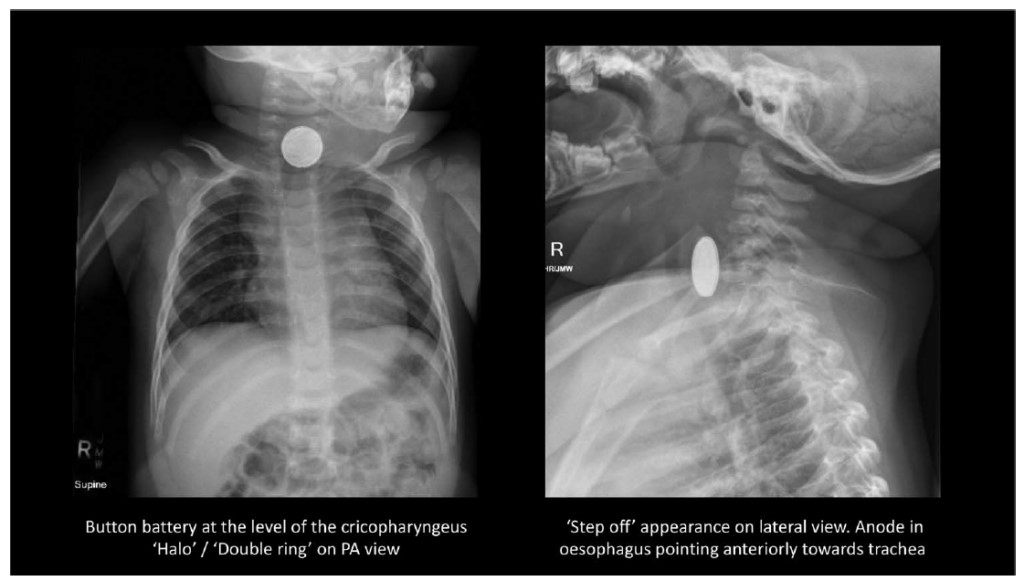

Si une ingestion de piles est suspectée, des radiographies simples de face, du cou, de la poitrine et de l'abdomen sont immédiatement indiquées.

Les BB peuvent ressembler à des pièces de monnaie sur les radiographies.

Les signes radiologiques distinctifs sont la présence d'un « halo » ou d'un « double anneau » sur des incidences radiologiques spécifiques que le médecin spécialiste en imagerie médicale maîtrise parfaitement.